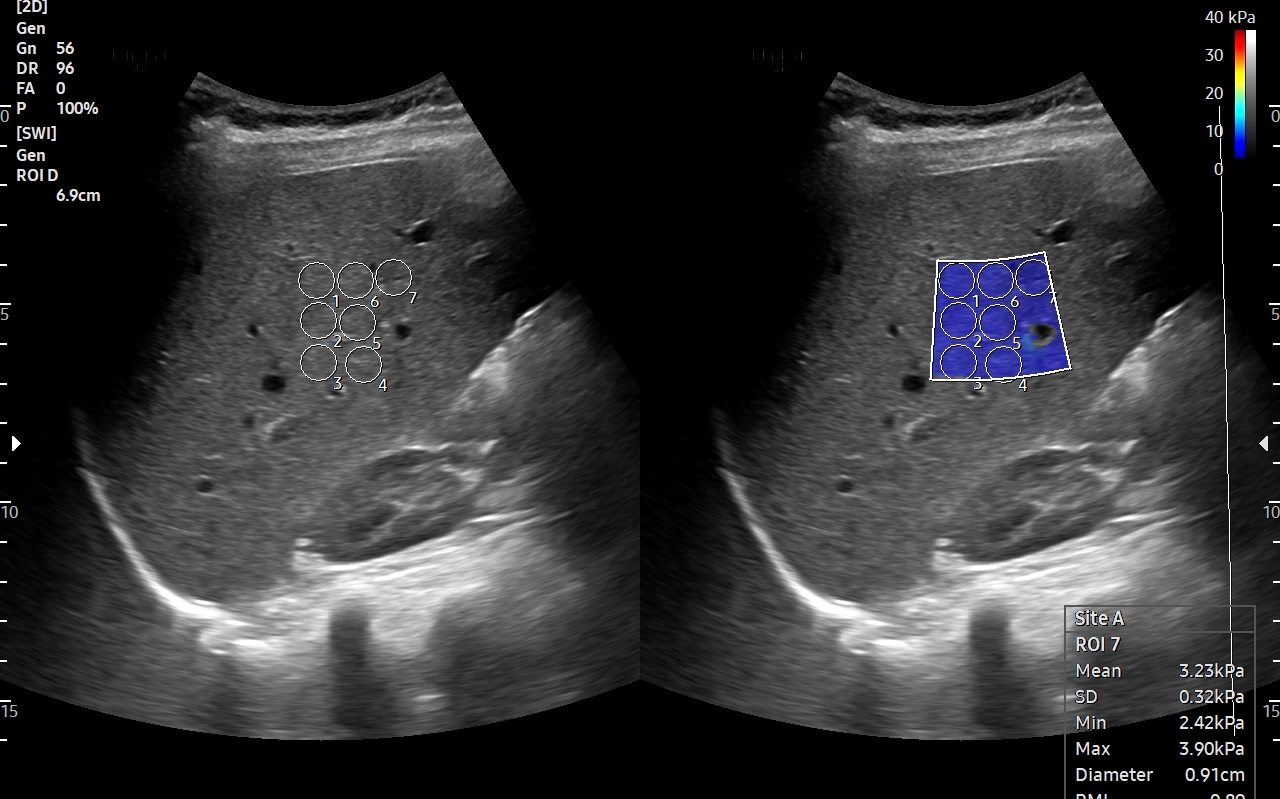

• elastografię 2D-SWE wątroby,

• badania Elastoscan guzów i tkanek,

• biologiczną ocenę nowotworów,